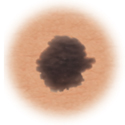

Moles (nevi)

Small skin marks caused by pigment-producing cells in the skin. Moles can be flat or raised, smooth or rough, and some contain hair. Most moles are dark brown or black, but some are skin-colored or yellowish. Moles can change over time and often respond to hormonal changes.

Most moles are benign and no treatment is needed. Some benign moles may develop into skin cancer (melanoma). See below for signs.

Normal mole.

This is a normal mole.